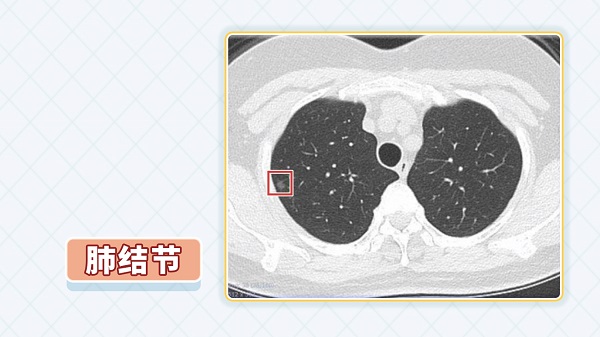

健康体检,或因为其他疾病去医院做检查,很多人做胸部CT时发现肺里长了小结节,因此很焦虑,担心会不会癌变,或者是不是恶性的。 首先,肺内长了结节肯定是不正常的,一旦发现要不要切除呢? 一、发现肺结节要不要切除? 如果结节很小,直径小于1厘米,没有典型的影像学征象,这种情况下,如果是初次发现可以定期观察,比如每三个月到半年复查一次胸部CT,看看结节大小、密度有没有变化,如果有变化尽早手术切除。 另外,如果有一些高危因素,比如有肿瘤家族史、长期吸烟,或者病人发现自己有肺结节后很焦虑,工作、生活都不能正常进行,这种情况建议尽快手术切除。 如果CT下发现结节有毛刺,有分叶,有血管征等,高度怀疑是恶性的情况下,需要取活检做病理来确诊,病理是诊断肺癌的金标准。 取活检一种就是在CT定位下穿刺,如果结节很小,只有5毫米、8毫米,穿刺是非常困难的。或者结节距离肺门、血管、气管比较近,穿刺也比较困难。 一般结节都是长在肺内,不是在支气管腔内,所以支气管镜、超声支气管镜也很难能取到。 目前有种很先进的设备,叫磁导航,是通过磁力来帮助取活检的,但这个设备是进口的,非常昂贵,一般很难普及。 所以现有的手段,高度怀疑肺结节是恶性的情况下,还是要通过胸腔镜手术来明确。 病理检查明确是恶性的,要及早手术切除。 二、肺结节病理检查是恶性的,能治好吗? 早期肺癌首选手术根治切除,效果是最好的,除非患者年龄很大,或者心肺功能很差,不能耐受手术。 不管是采用传统的开胸手术,还是胸腔镜微创手术,都是可以的,根治切除范围是一样的,由于微创技术的发展,病人的痛苦更小了,恢复也更快了。 早期肺癌手术可以达到根治,所谓根治,从医学角度来说,恶性肿瘤是以三年,五年生存率来算的。 比如原位癌或者微浸润癌,或者癌前病变,做根治性切除五年以上生存率是100%,效果非常好。比如浸润性肺癌,有转移的可能,早期根治切除以后,五年以上生存率可达到85%-90%。 所以早期肺癌治愈率是很高的。 虽然说早期肺癌治愈率很高,但是早期肺癌不容易发现,因为早期往往没有症状,特别是小结节,单靠症状早期发现是不现实的,那么,就要依靠体检或筛查。 三、建议哪些人群定期做肺癌筛查? 要想早期发现肺癌,建议40岁以上的人群每年做一次胸部CT。 以前肺癌的发生年龄可能在60岁以上,或者70岁以上,老年人居多,但随着瘤谱的改变,我们发现肺癌有年轻化的趋势,35-50岁的人群,肺癌发病率在逐年升高。 一般来说40岁以下的人群,得肺癌的几率相对比较低,我们不可能做到全员去做肺癌的体检筛查,还是建议40岁以上的人群每年做一次胸部CT。 另外,肺癌的高危人群,比如长期吸烟,有肺癌家族史的人群。肺癌并不是遗传病,父母、直系亲属有得肺癌的,由于基因的缘故,或者说肿瘤的易感性,可能是肺癌的高危人群,这部分人群更要建议每年做一次胸部CT来筛查。 那么,肺癌的高危人群,每年做一次胸部CT就可以吗? 我们知道CT的射线扫描剂量,一般来说相当于几十张胸片的剂量,频繁做胸部CT是不合适的。另外,每三个月或每半年做一次胸部CT也不是很现实。所以每年做一次胸部CT是很有必要的,因为肿瘤它有一个倍增的时间,几年都不做一次恐怕是不行的。 |